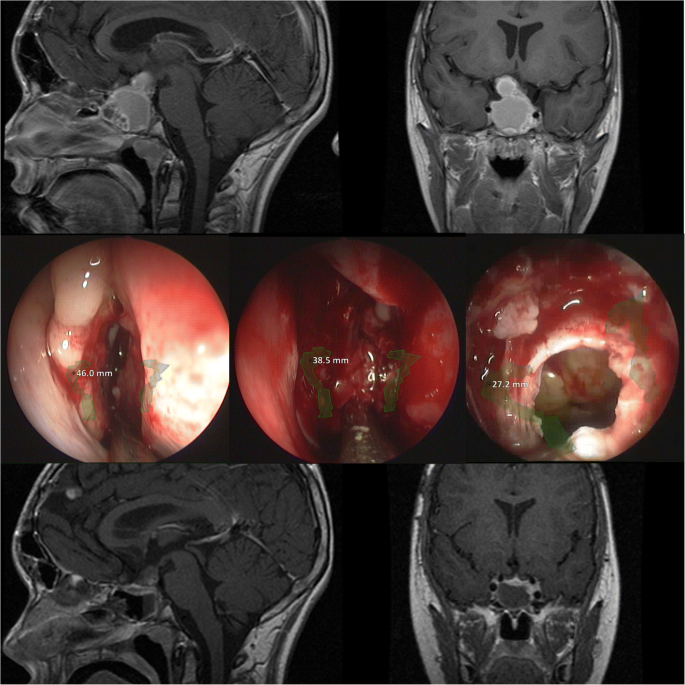

Case example of a patient with a craniopharyngioma: Upper row: preoperative MRI (T1 sagittal and coronal post-gadolinium sequences). Middle row: intraoperative endoscopic view at different anatomic levels of the turbinates, the sphenoid cavity and the sella with AR information indicating the carotid arteries. Lower row: postoperative MRI (T1 sagittal and coronal post-gadolinium sequences)